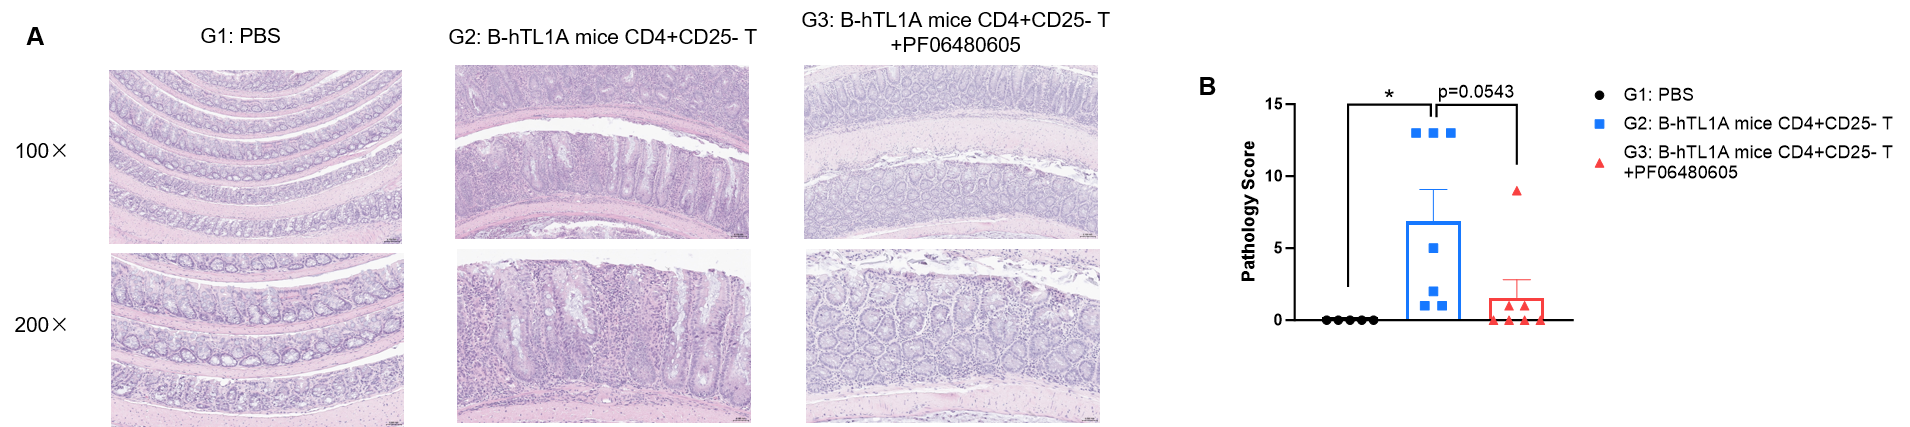

CD4+CD25- T cells were isolated from the spleens of B-hTL1A mice using commercial kits. B-Rag2 KO animals in groups G2-G3 were injected with 6×105 CD4+CD25- T cells, while B-Rag2 KO animals in group G1 were injected with the same volume of PBS. Animals in group G3 were given 25 mg/kg of anti-TL1A antibody PF06480605 twice a week. (A) H&E staining of colon tissue. (B) Pathological score. Administration of anti-TL1A antibody PF06480605 improved T cells-induced colitis, Two-way ANOVA or one-way ANOVA was used for multiple comparisons, with each group compared to group G2. Values are expressed as mean ± SEM. *p<0.05, **p<0.01, ***p<0.001, ****p<0.0001.